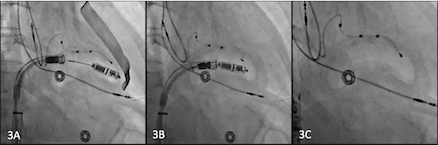

Leadless cardiac pacemakers (LCP) have evolved as an excellent alternative to transvenous pacemaker (TVPM) for bradycardia therapy with excellent safety and efficacy outcomes. MicraTM was the first commercially available LCP. The device attaches to the right ventricular myocardium with four Nitinol FlexFix™tines. Its inherent design poses problems with retrievability. This leads to many devices being turned off and left behind in the right ventricle at the end of its life. The Aveir retrieval catheter was recently launched as part of the Aveir family of LCP and has a tri-loop snare re-docking mechanism, steerability, and protective sleeve.

We present a case series of 8 successful retrievals of Micra™ LCP using the Aveir™ retrieval catheter. Four patients had the LCP removed during upgrade to cardiac resynchronization therapy and the other four had the LCP removed at the time of replacement of the LCP at device end-of-life. The mean age of the cohort was 72.6±9.4 years (62.5% female). The average age of the retrieved LCP was 4 years and 4 months with the oldest device being in place for 7 years and 7 months. Median retrieval time, defined as time from retrieval catheter in to retrieval catheter out, was 4.8±2.4 minutes. In 100% of the cases the LCP was successfully retrieved in its entirety via femoral venous access. There were no intra- or post-procedural complications, including vascular complications, pericardial effusions, right ventricular dysfunction or worsening tricuspid regurgitation. At six months follow up, patients continued to remain free of the above complications.

This case series demonstrates the safety and feasibility of using the Aveir™ retrieval catheter for extraction of the Micra™ LCP device in lieu of abandonment. Additional studies should be considered to assess the risk and benefits of abandoning the device in the right ventricle extraction of the LCP with this novel technique. The authors acknowledge the steep learning curve associated with this procedure. Further multicenter analysis of this technique is necessary to determine its generalizability.